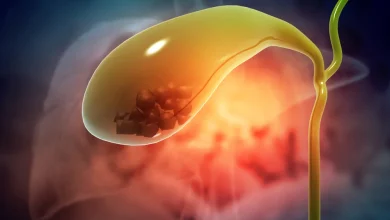

سنگ های صفرا معمولا اصلی ترین مشکل کیسه صفرا می باشند که این سنگ های کوچک می تواند در گوارش فرد مشکل ایجاد کند.

کیسه صفرا یک اندام کوچک در بالای میان تنه است منظور از میان تنه همان شکم است. در مورد وظایف و کار کیسه صفرا در بدن باید گفت کیسه صفرا تمام مایعات بدن را جمع آوری کرده و آن ها را ذخیره می کند و به هضم غذا نیز کمک می کند. مواد غذایی سفت و سخت گاهی اوقات می توانند به سنگ هایی در بدن تبدیل شوند که این وضعیت برای افراد زیادی اتفاق می افتد.

سنگ های صفرا معمولا اصلی ترین مشکل کیسه صفرا می باشند که این سنگ های کوچک می تواند در گوارش فرد مشکل ایجاد کند.

علت برداشتن کیسه صفرا

همانگونه که در بخش سلامت نمناک عنوان کرده ایم ترشحات صفراوی در واقع مجموعه ای از چربی ها، املاح صفراوی و بعضی مواد زاید دفعی کبد است که چنانچه شرایط نامساعدی اتفاق بیفتد در مسیر عبور صفرا که همان مجاری صفراوی است موادی که به طور عمده از جنس چربی متراکم و همراه با املاح می باشند رسوب کرده و منجر به ایجاد سنگ صفراوی می شود و همین این سنگ ها می توانند منجربه انسداد مجاری صفراوی و در نهایت التهاب کیسه صفرا شوند که درمان این مشکل برداشتن کیسه صفرا است.

سنگ های کیسه صفرا می توانند یک عدد و بسیار ریز باشند . در بعضی از مواقع این سنگ ها چند تا و بزرگ هستند . در هر صورت فرقی ندارد که تعداد و سایز این سنگ ها چقدر است و هر چقدر کم و خفیف هم می تواند فرد را به مرحله جراحی بکشاند زیرا اگر اقدام به برداشتن و رفع این مشکل نکنید ، راه صفرا مسدود نمی شود و نمی تواند ارتباط خود را با کبد حفظ کند و التهابات دردناکی را به وجود می آورد که به آن التهاب کیسه صفرا می گویند.